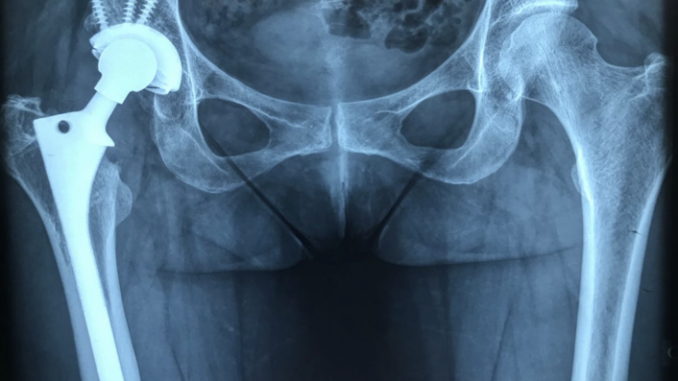

Existem diversos tipos de próteses de quadril, sendo que a mais utilizada é a prótese total de quadril que possui um metal recoberto internamente de plástico ou cerâmica. Na cirurgia é feita uma substituição da articulação doente e disfuncional para uma articulação nova que devolve mobilidade, funcionalidade e elimina as dores do paciente.